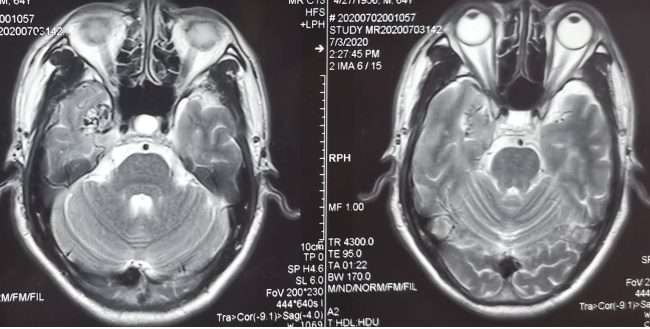

外院头颅CT示右侧颞叶钙化灶,头颅MRI示见右侧颞叶流空信号,考虑动静脉畸形。

入院后脑血管造影检查提示:右侧颞叶动静脉畸形,由右侧大脑中动脉两分支血管参与供血,右侧大脑后动脉一分支血管参与供血,畸形团大小约1.1*1.3cm,通过侧裂静脉经皮层静脉引流入上矢状窦前部;并可见右侧大脑后动脉供血畸形团的分支血管血流相关性动脉瘤两枚。